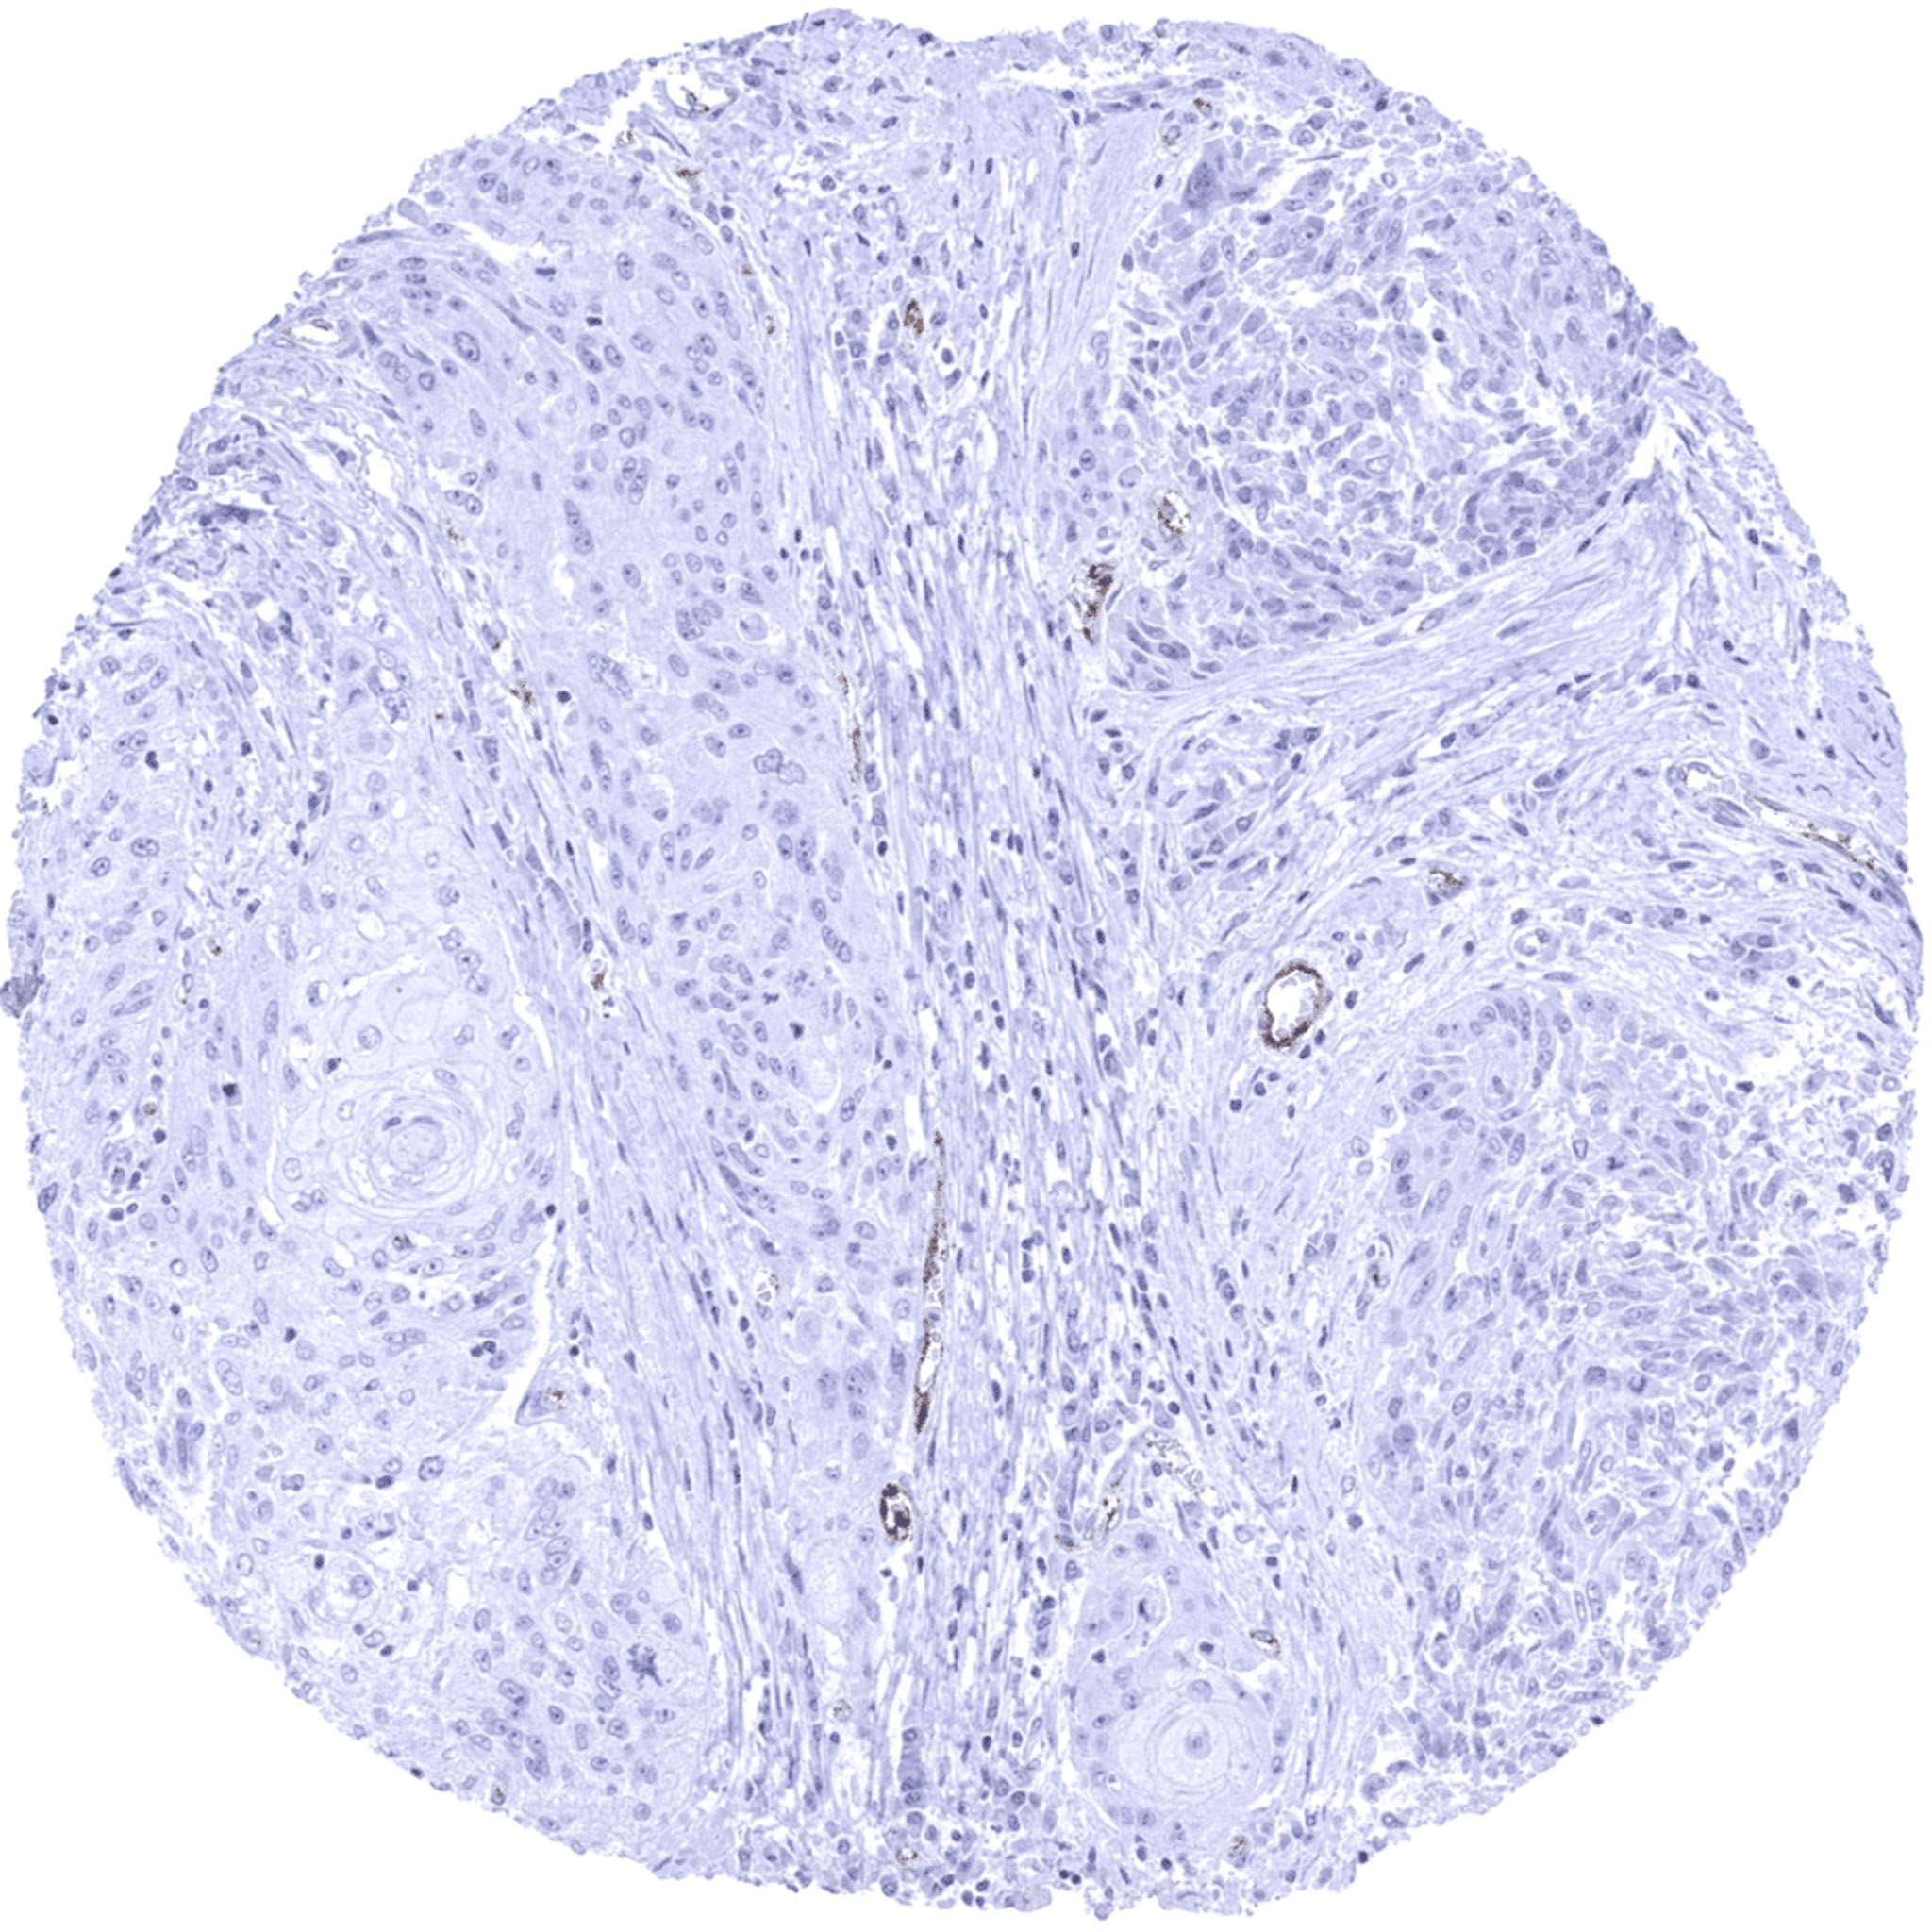

Oral cavity- Squamous cell carcinoma depicting variable intensities of VWF staining in a fraction of small intratumoral vessels.